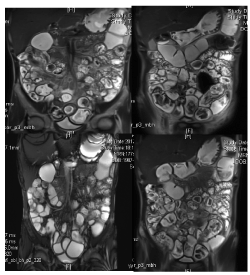

Figure 3. MRE; the ileum many Segmental thickening and abnormal strengthening, Conhon Disease. Between the midriff intestinal canal abnormal signal nodule, considering as swollen lymph nodes